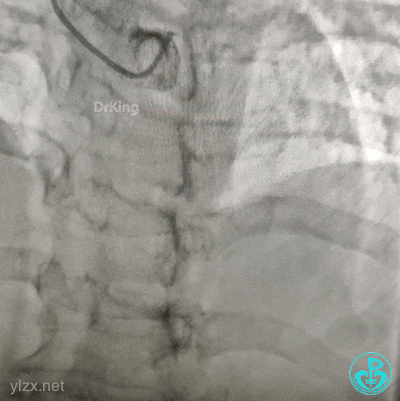

果断更换指引导管。

指引导管刚刚送到升主动脉,患者便发生抽搐、呼之不应,立即胸外按压几次后,患者清醒了,快速置入IABP。造影发现整个前壁不怎么搏动了。

血压低,去甲肾上腺素8mg,25ml/h微量泵入,血压高时可维持在140/80mmHg左右,一直到手术结束。